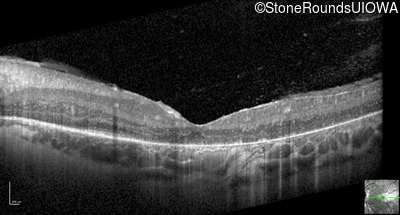

Optical Coherence Tomography - Left - 20/80 -1

Exemplar / OCT Stack